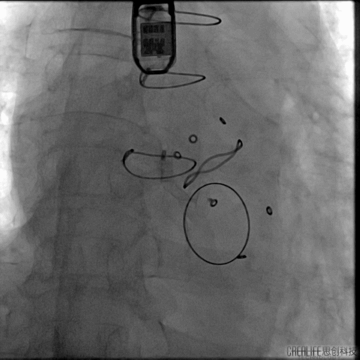

瓣上造影

造影可见主漏及无窦附近明显瓣周漏;

血管塞封堵

12mm三支血管塞置入

术中食道超声确认满意后释放血管塞